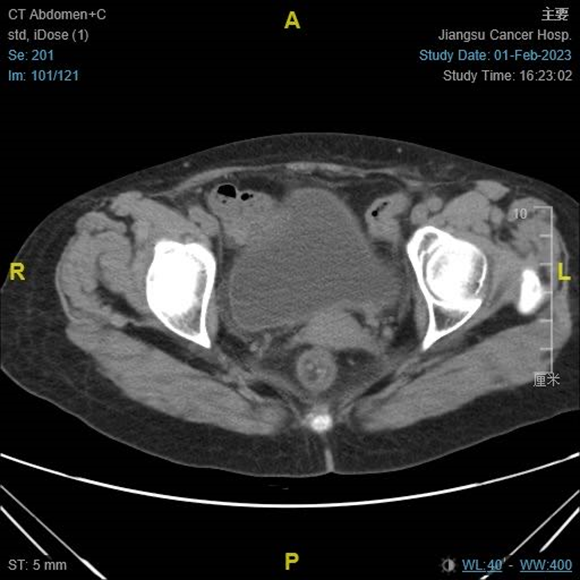

CT复查:2023-2-1,阴道后壁复发灶完全退缩。

图11. CT复查提示阴道后壁复发灶完全退缩